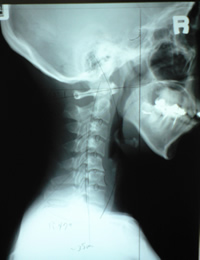

- レントゲンを参考に説明(最初にレントゲンを持参されての来院される方がより明確な治療が行えます。)

- レントゲン像を確認・YPバイタルリアクターによるさらに細かいチェックをし施術